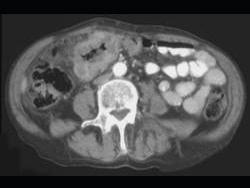

问题 男,45岁,右下腹胀痛、并可触及质硬包块,请结合图像选择最可能诊断 ( )

选项 A、结肠淋巴瘤 B、慢性溃疡性结肠炎 C、结肠癌 D、肠结核 E、结肠crohn病

答案 C